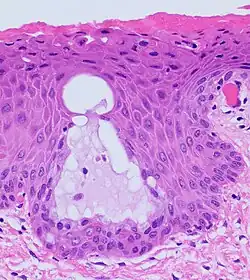

The endocervical mucosa is about 3 mm (0.12 in) thick and lined with a single layer of columnar mucous cells. It contains numerous tubular mucous glands, which empty viscous alkaline mucus into the lumen.[4] In contrast, the ectocervix is covered with nonkeratinized stratified squamous epithelium,[4] which resembles the squamous epithelium lining the vagina.[17]: 41 The junction between these two types of epithelia is called the squamocolumnar junction.[17]: 408–11 Underlying both types of epithelium is a tough layer of collagen.[18] The mucosa of the endocervix is not shed during menstruation. The cervix has more fibrous tissue, including collagen and elastin, than the rest of the uterus.[4]

The squamocolumnar junction of the cervix, with abrupt transition: The ectocervix, with its stratified squamous epithelium, is visible on the left. Simple columnar epithelium, typical of the endocervix, is visible on the right. A layer of connective tissue is visible under both types of epithelium.

In prepubertal girls, the functional squamocolumnar junction is just within the cervical canal.[17]: 411 Upon entering puberty, due to hormonal influence, and during pregnancy, the columnar epithelium extends outward over the ectocervix as the cervix everts.[15]: 106 Hence, this also causes the squamocolumnar junction to move outwards onto the vaginal portion of the cervix, where it is exposed to the acidic vaginal environment.[15]: 106 [17]: 411 The exposed columnar epithelium can undergo physiological metaplasia and change to tougher metaplastic squamous epithelium in days or weeks,[17]: 25 which is very similar to the original squamous epithelium when mature.[17]: 411 The new squamocolumnar junction is therefore internal to the original squamocolumnar junction, and the zone of unstable epithelium between the two junctions is called the transformation zone of the cervix.[17]: 411 Histologically, the transformation zone is generally defined as surface squamous epithelium with surface columnar epithelium or stromal glands/crypts, or both.[20]

Nabothian cysts (or Nabothian follicles) form in the transformation zone where the lining of metaplastic epithelium has replaced mucous epithelium and caused a strangulation of the outlet of some of the mucous glands.[17]: 410–411 A buildup of mucus in the glands forms Nabothian cysts, usually less than about 5 mm (0.20 in) in diameter,[4] which are considered physiological rather than pathological.[17]: 411 Both gland openings and Nabothian cysts are helpful to identify the transformation zone.[15]: 106